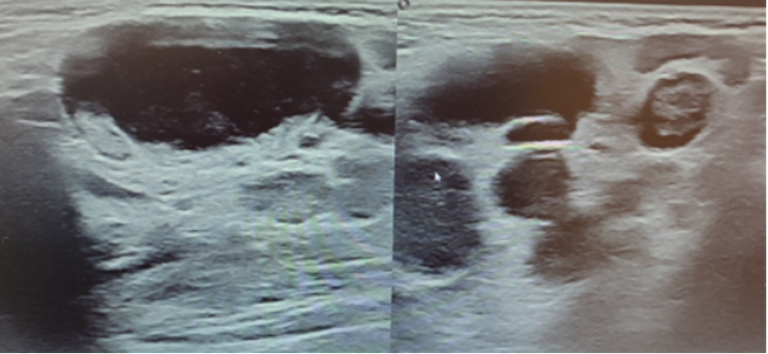

L’ecografia di cute e tessuti molli evidenzia formazione ovalare ipocogena di 2,4x1,2 cm parzialmente colliquata, priva di ilo adiposo e con vascolarizzazione sia periferica che centrale, in prima ipotesi riferibile a linfonodo patologico e concomitante imbibizione edematosa dell’adipe limitrofo con ulteriori piccole formazioni linfonodali con le medesime caratteristiche ecografiche (Figura 1 e Figura 2).